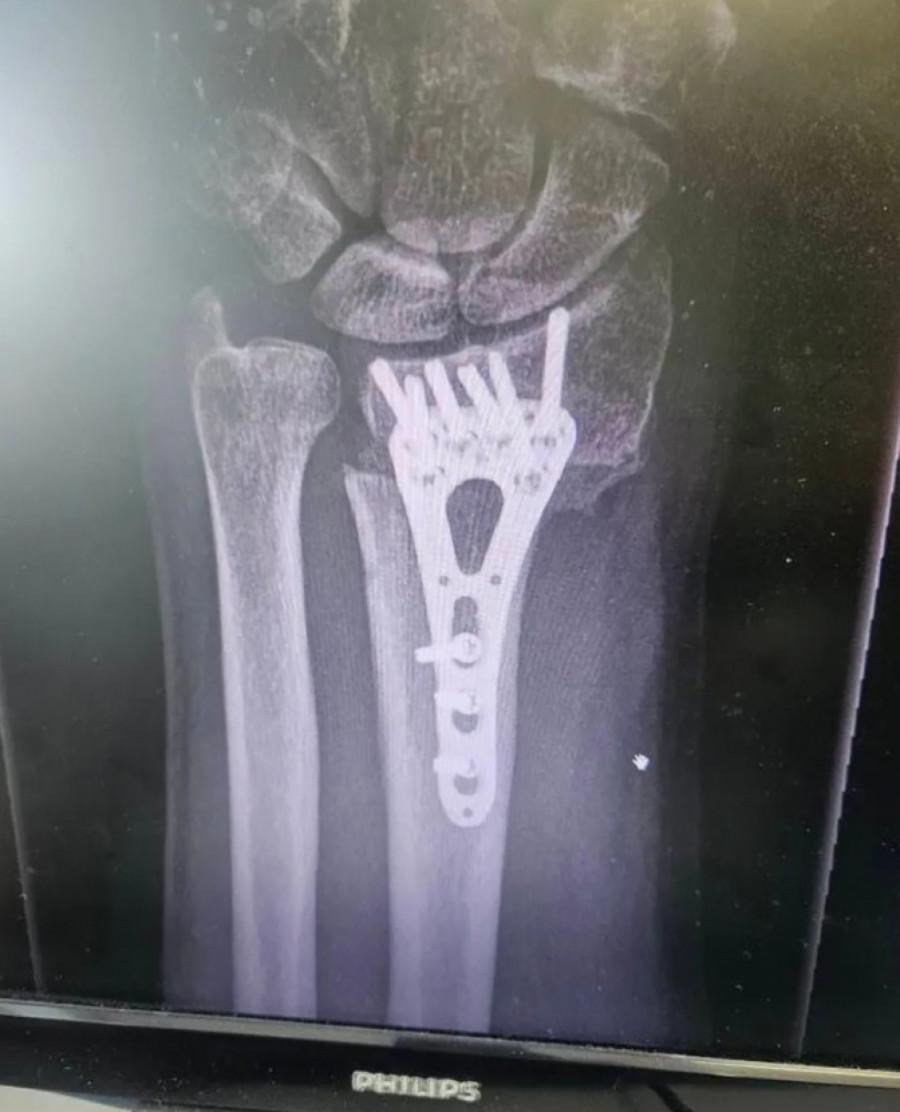

Voditelj Aleksandar Stanković otkrio je da je hitno operisan nakon što je zadobio povredu.

Na svom Instagram profilu je objavio fotografiju preloma ruke do kog je došlo pre tri meseca, te pokazao kako je tekla faza oporavka.

- Ovako je to izgledalo pre tri meseca, a danas je sve u redu. Slomio sam ruku i operisali su me u Opštoj bolnici Sisak. Ruka je zarasla i hvala im što su svoj posao odradili profesionalno i s ljubavlju! - istakao je voditelj.